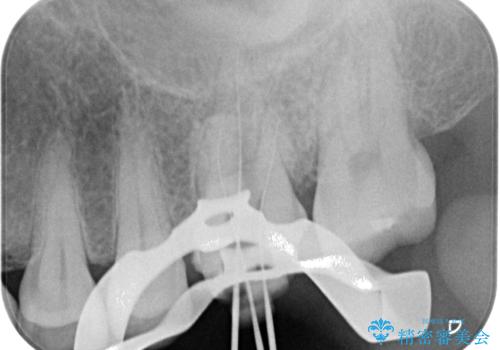

診査を行った結果、まずは根管治療を行うこととしました。

咬み合わせが非常に強く、臼歯のみに咬合力が集中している咬み合わせだったので、根管治療後はPGAクラウン(白金加金合金クラウン)にて補綴する治療計画となりました。

初回の根管治療を終えた2日後には膿の出口が消失し、咬んだときの不快な痛みもなくなりました。